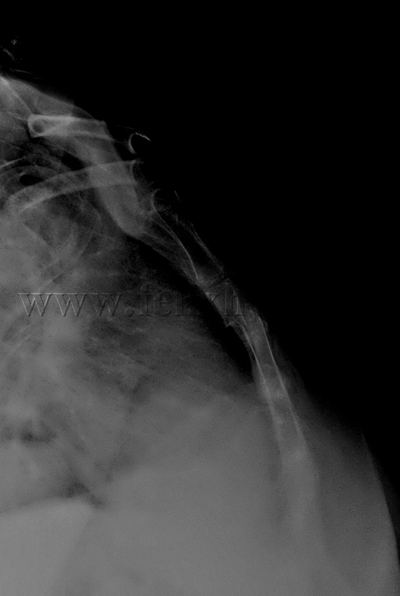

Fractura de esternón